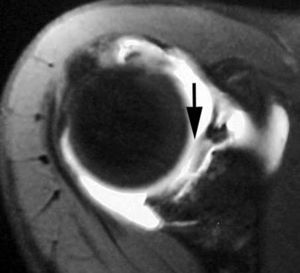

Rotura simple del labio glenoideo posterior

Esta lesión se produce a consecuencia de una dislocación posterior y puede acompañarse de una fractura por impactación de la parte anterior de la cabeza humeral (Hill Sachs invertido) (fig. 13).

Fig. 13.--Rotura del labio glenoideo posterior. Artrorresonancia axial T1 con supresión grasa que revela una rotura del labio glenoideo posterior (flecha).